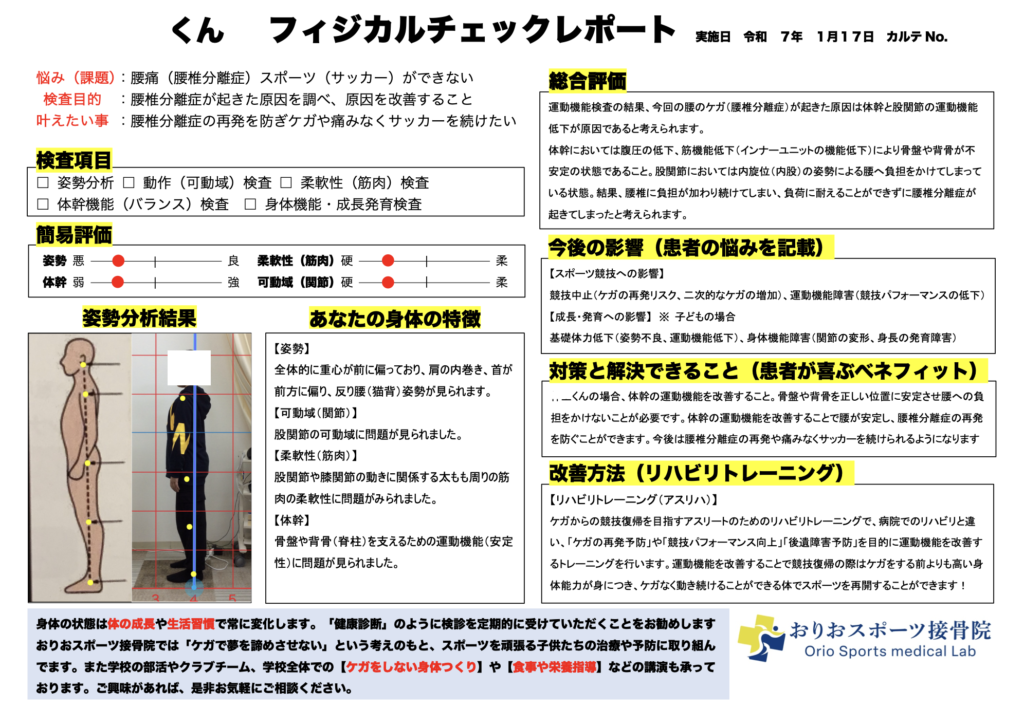

フィジカルチェックで体の問題点を洗い出す

痛みがある程度落ち着いてきたら、次は「なぜケガをしたのか」という根本原因を調べるための検査を行います。これが「フィジカルチェック(運動機能検査)」です。

フィジカルチェックでは、姿勢、柔軟性、筋力、バランス、体幹機能など、体の様々な機能を総合的に評価します。これにより、ケガをしやすい体の使い方や、弱い部分、硬い部分などが明らかになります。

S様の場合、足首の柔軟性が著しく低下していることに加え、体幹の安定性にも課題があることが分かりました。体幹が弱いと、ジャンプの着地時に体がぶれやすく、足首や膝に余計な負担がかかります。

また、片足立ちのバランステストでは、右足で立った時に体が大きく揺れ、バランスを保つのが難しい様子が見られました。これも、足首の安定性が低下していることの表れです。

成長発育検査でケガのリスクを予測

成長期のお子さんには、成長発育検査も実施しています。これは、身長の伸び率を測定し、今後どのくらい身長が伸びるか、ケガが起こりやすい時期がいつ頃かを予測する検査です。

身長が急激に伸びる時期は、クラムジー現象が起こりやすく、ケガのリスクが高まります。この時期を事前に予測しておくことで、練習量を調整したり、ケアを強化したりすることができます。

S様の成長発育検査の結果、今後1年ほどは身長の伸びが大きい時期が続くと予測されました。そのため、この時期は特に柔軟性の維持やバランストレーニングを重視し、ケガの予防に努めることが重要です。

一人ひとりに合わせた改善プログラム

フィジカルチェックと成長発育検査の結果をもとに、S様専用の改善プログラムを作成しました。このプログラムには、以下のような内容が含まれます。

足首の柔軟性を高めるストレッチ

毎日自宅で行うストレッチメニューを指定し、継続してもらいます。

体幹トレーニング

プランクやサイドプランクなど、体幹を安定させるトレーニングを週3回程度行います。

バランストレーニング

片足立ちやバランスボードを使ったトレーニングで、足首の安定性を高めます。

ジャンプ動作の改善

着地時の膝の使い方、体重移動の仕方など、正しいジャンプ動作を練習します。

これらのトレーニングは、お子さんの年齢や体力、競技レベルに合わせて調整します。無理なく続けられることが、効果を出すために最も重要です。